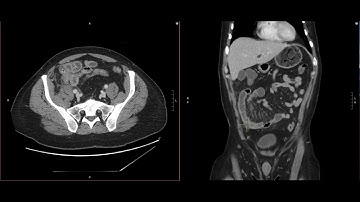

Abdominal Imaging Call Prep Cases: Acute Uncomplicated Appendicitis (CT) Case 3 Discussion